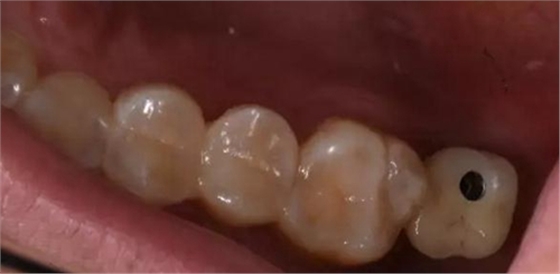

病例2:T女士,42歲。左上后牙缺失3年。就診要求恢復咀嚼功能。

X片上可見T女士左上后牙缺失。根據(jù)患者口內和全身狀況。制定計劃為:右上后牙種植修復。